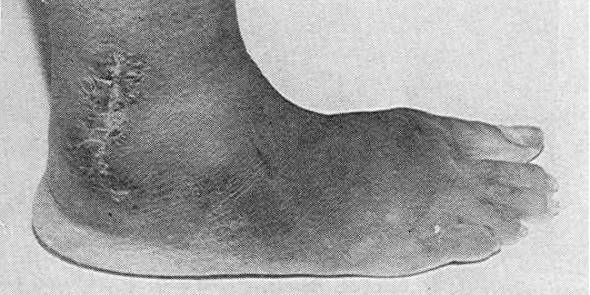

No special stain is needed because grains are quite visible in sections stained with the routine haematoxylin and eosin (H/E ).They take a light eosinophilic stain and usually seen in the middle of polymorphonuclear leucocytes. Grains may be circular or oval in shape, composed of compact hyphae with or without spores and may be partly vesicular  (Fig.4).They measure about 150 x 70 m. Special stains e.g periodic acid schiff and silver reveal the details of colonies showing individual segmented hyphae.

Figure 4: Vesicular pale grain of A.flavus in histological section, H/E stain x 800.